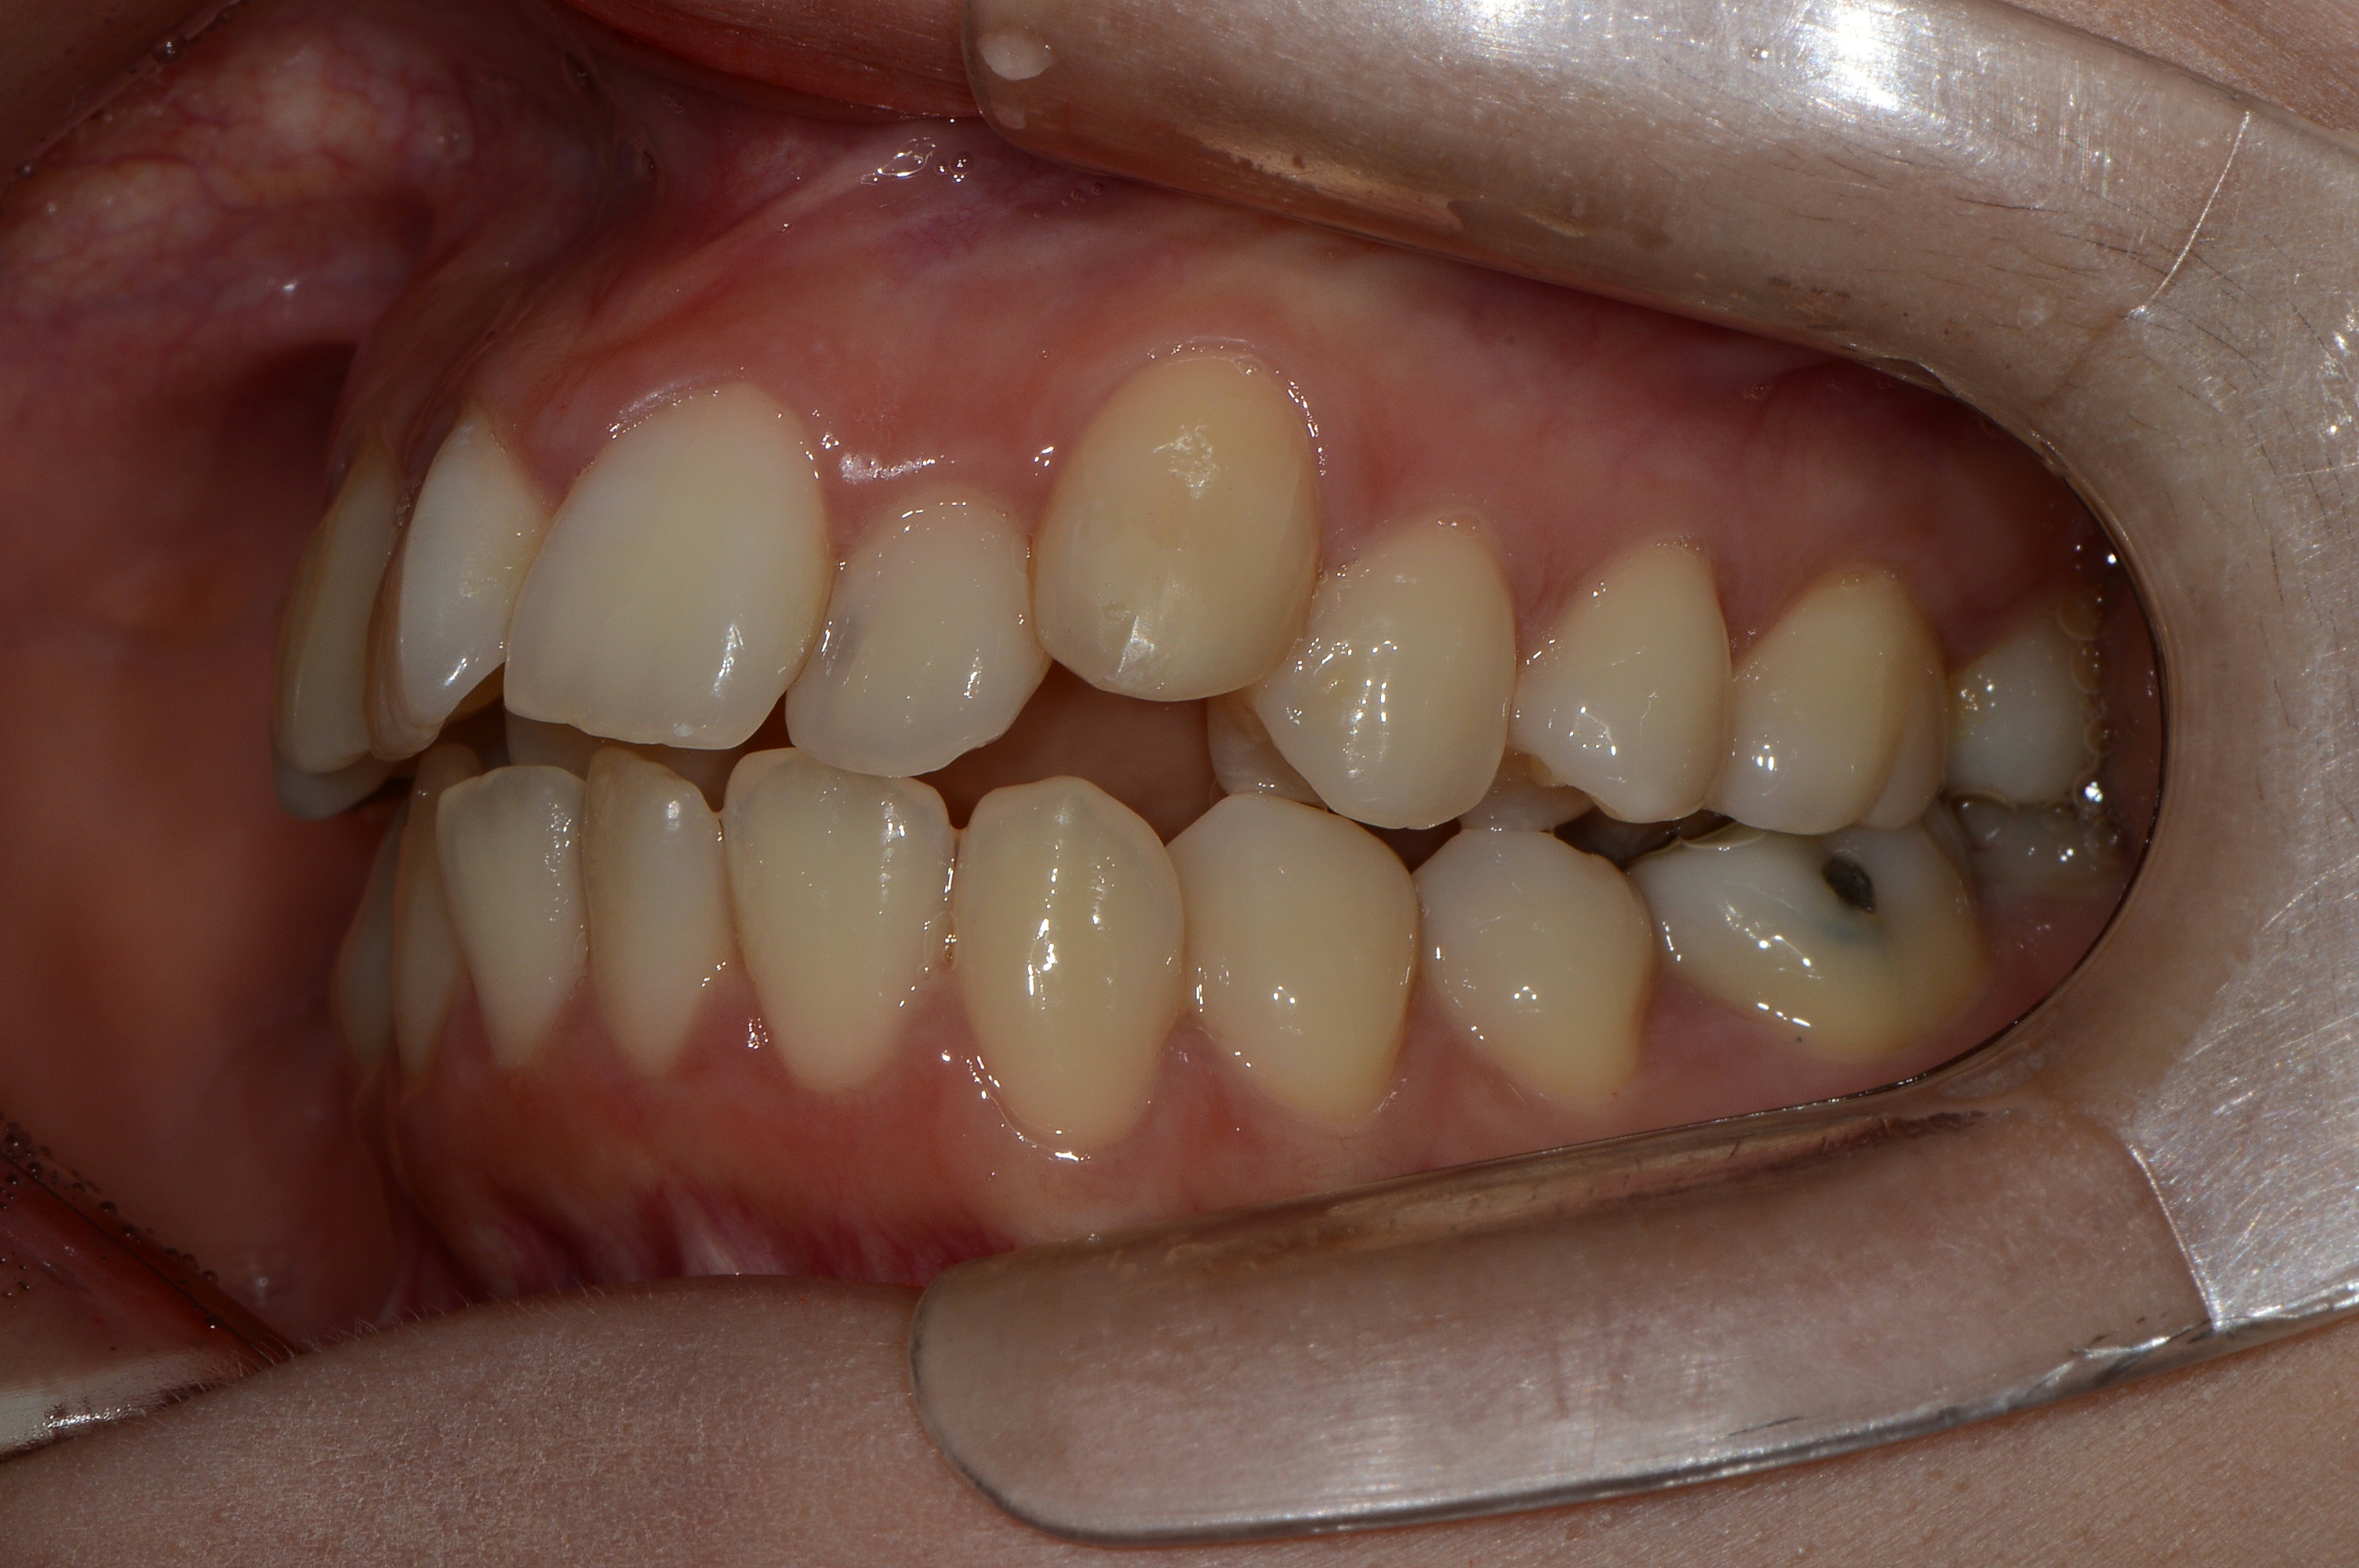

치료 후 사진입니다.